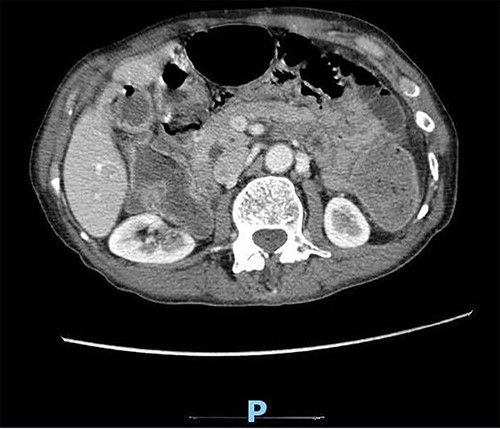

Upon clinical examination, the patient was vitally stable. Abdominal examination revealed a distended abdomen with generalized tenderness. Digital rectal examination revealed an empty rectum with no palpable masses. Laboratory investigations were unremarkable (Table 1). Abdominal X-ray was done (Fig. 2) and showed dilated large bowel loops suggestive of bowel obstruction. Enhanced CT scan of the abdomen and pelvis was obtained (Figs 3–5) and showed a dilated large bowel loop, with air fluid level. A 2.5-cm gallstone was noted, impacting the sigmoid colon and causing partial large bowel obstruction. There was evidence of pneumobilia with air foci within the gallbladder with a suspected fistula with the hepatic flexure.

Enhanced CT scan of the abdomen showing a gallbladder stone impacted at the sigmoid colon, with a significantly enlarged prostate causing narrowing of the rectosigmoid junction (sagittal view).